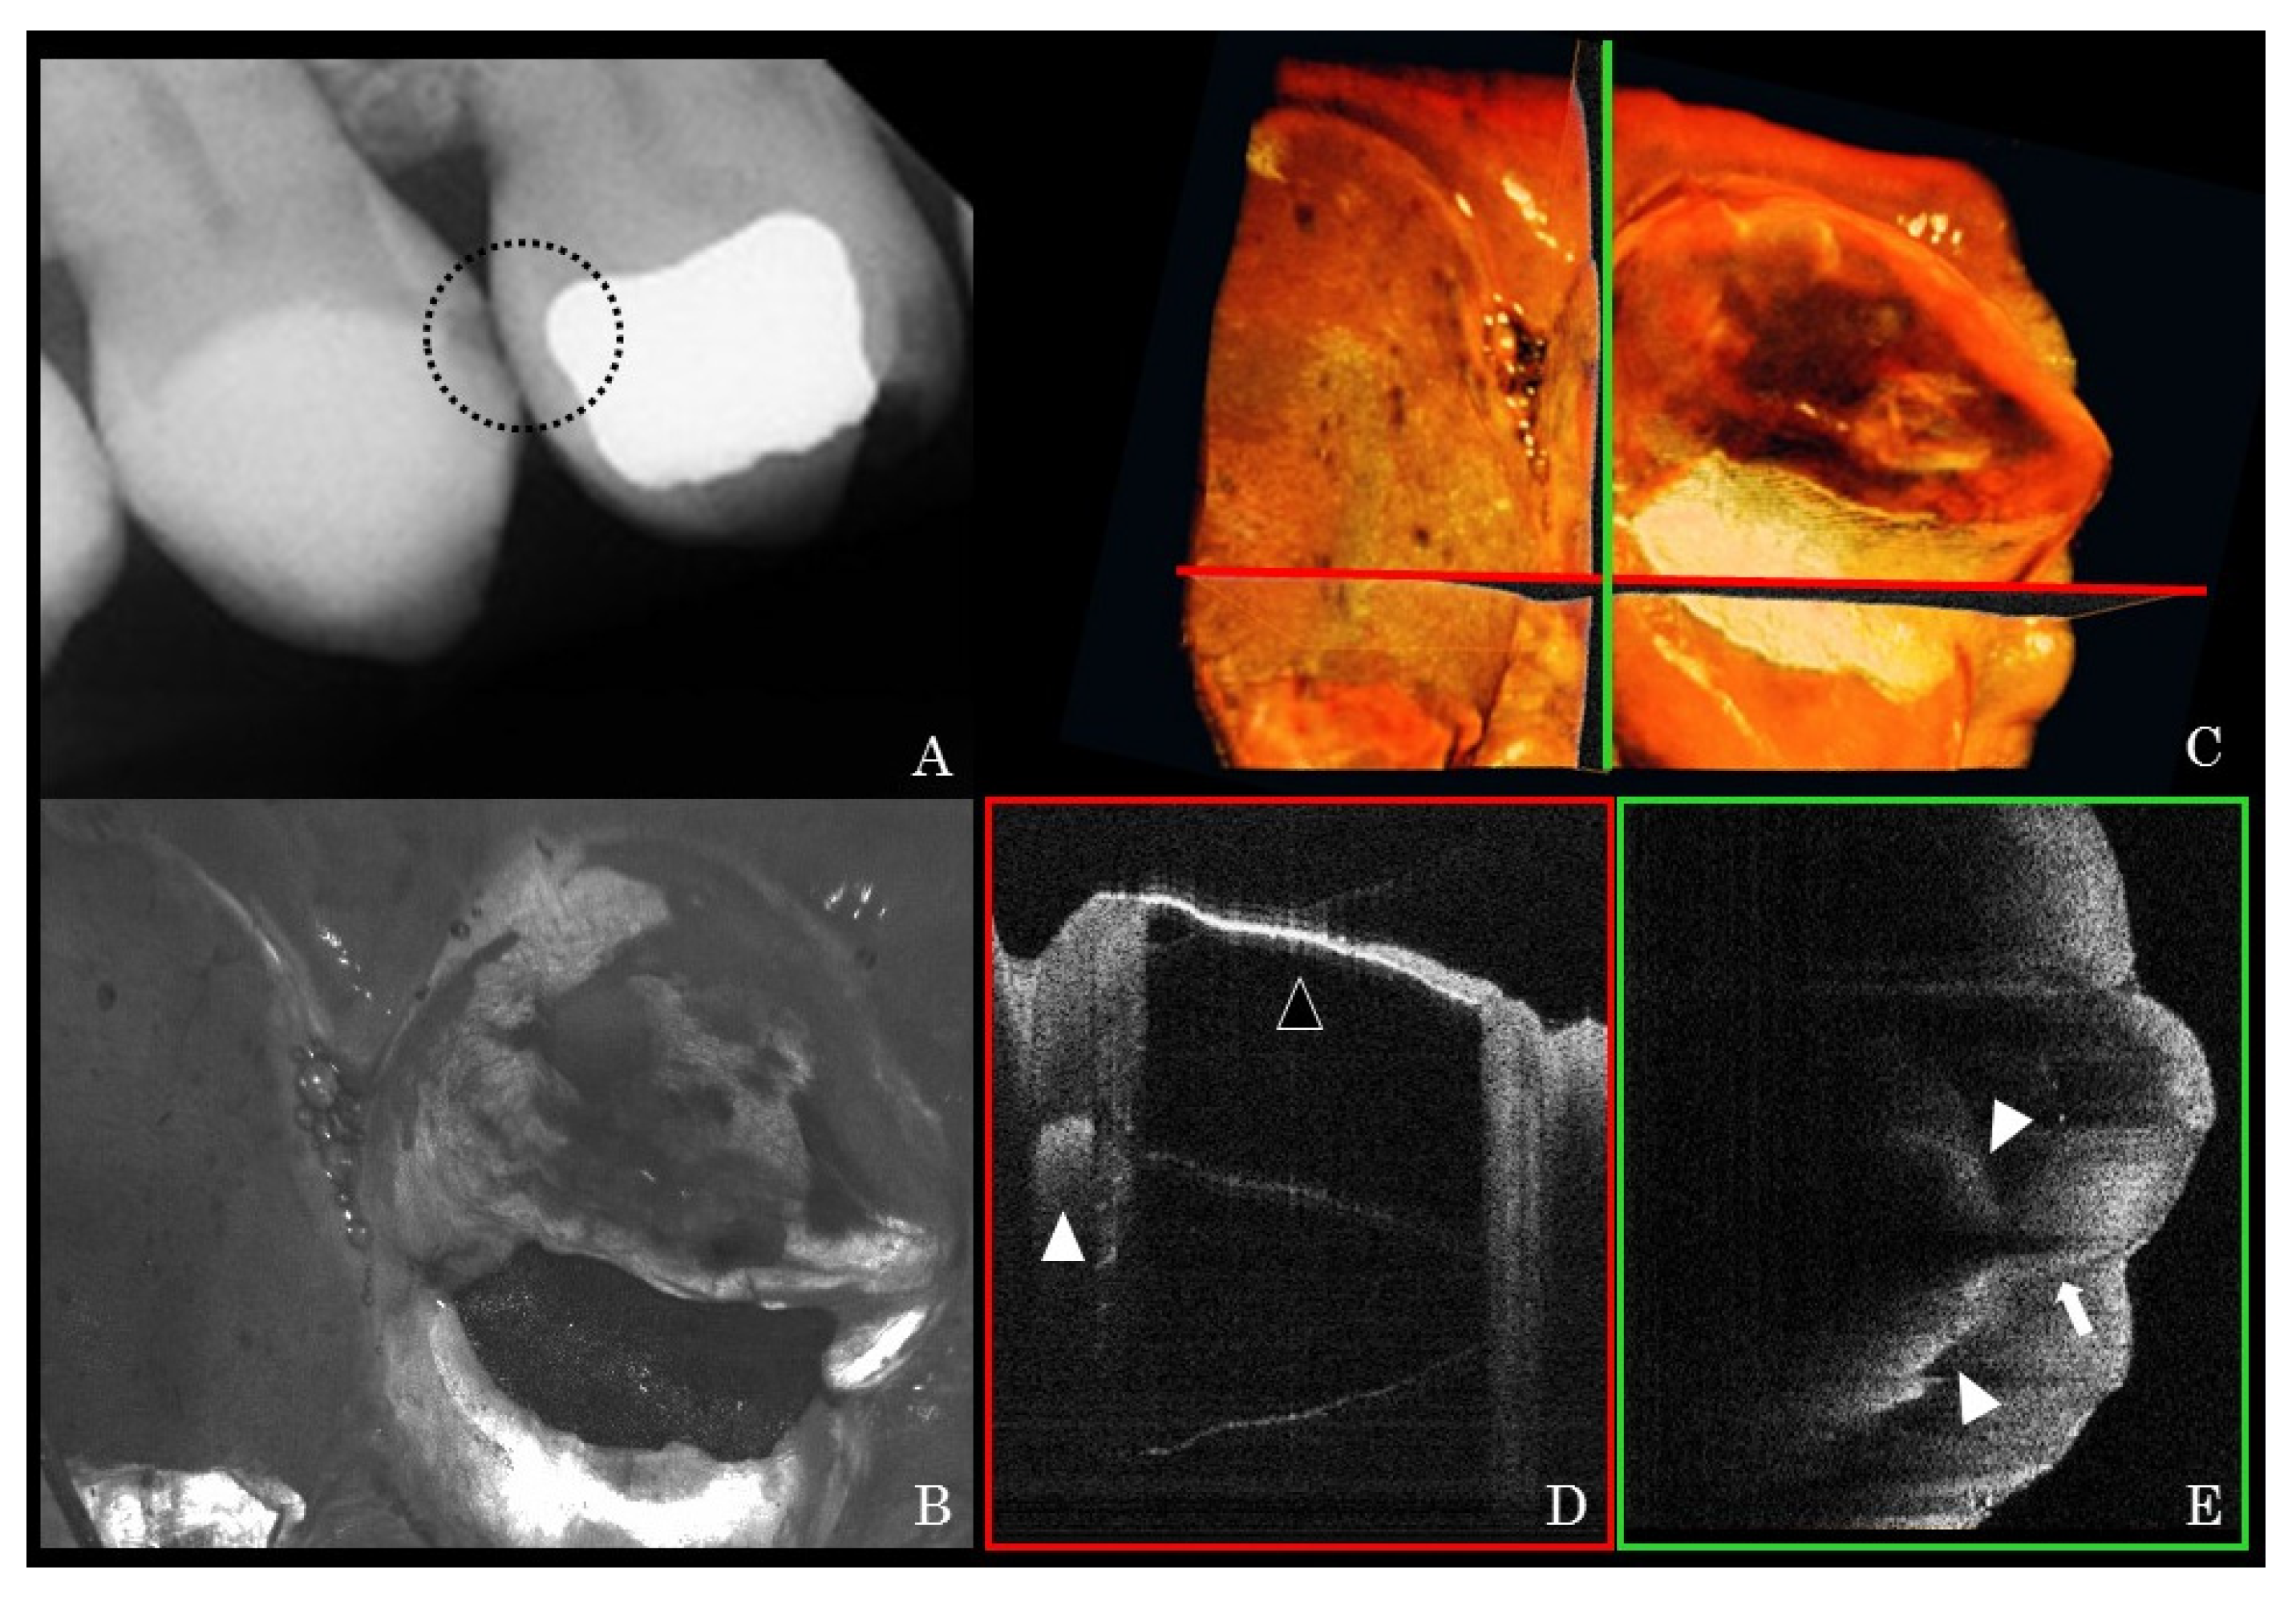

3. Results